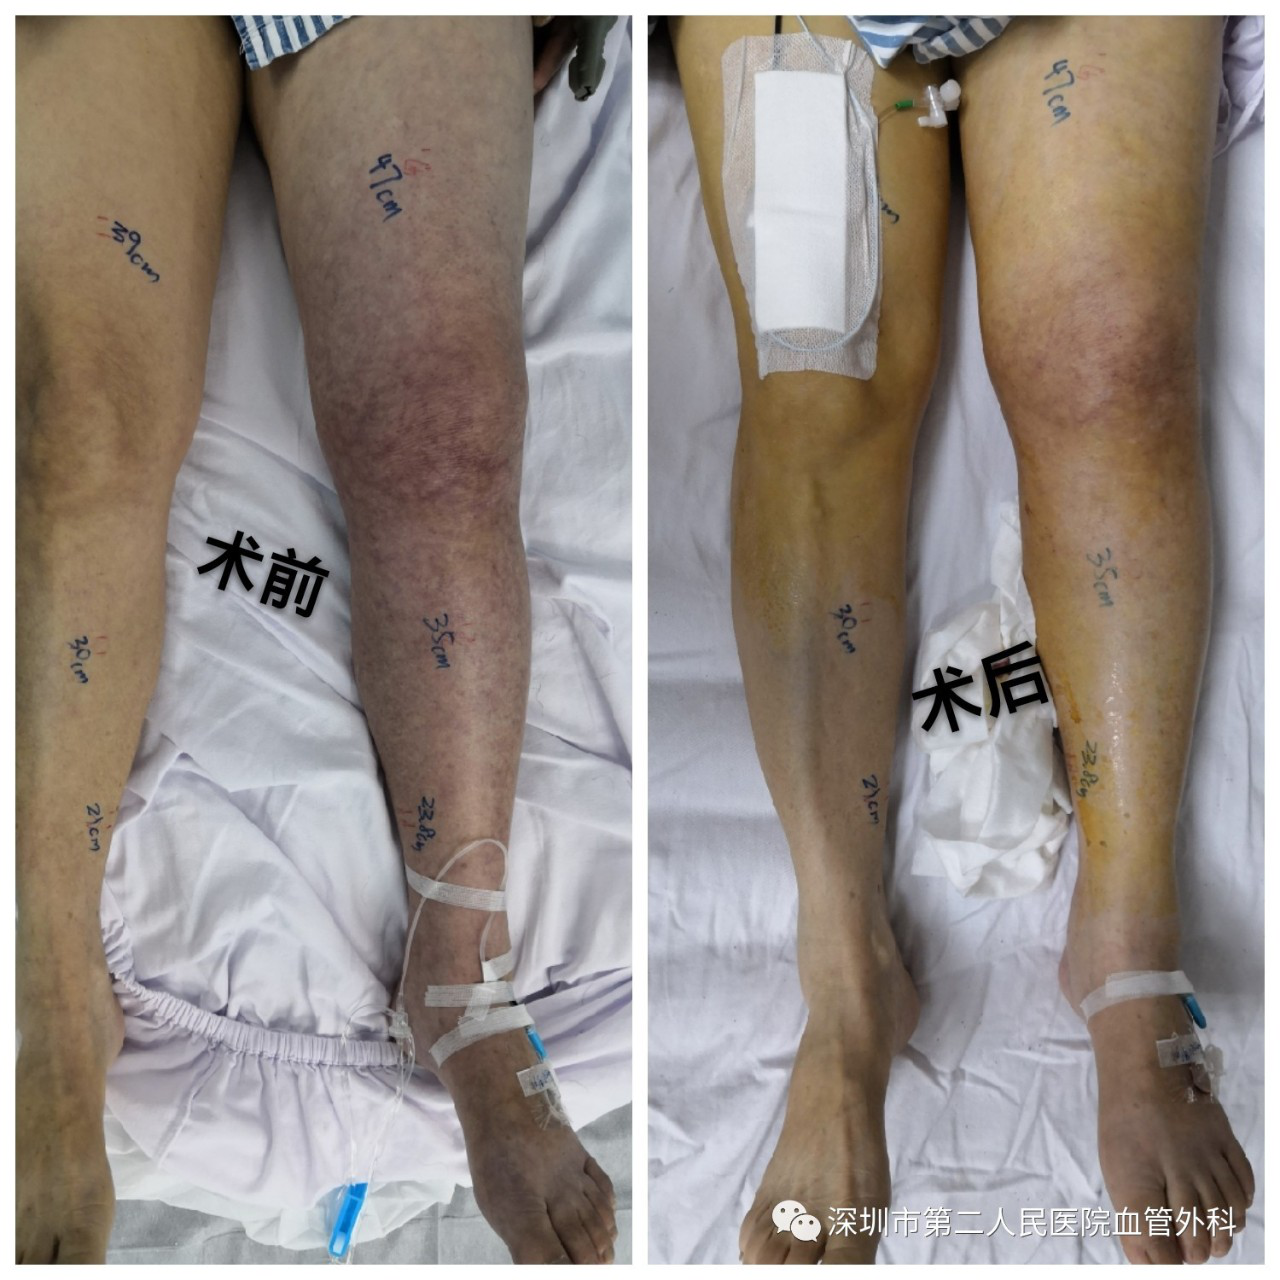

下肢深静脉血栓形成后,腿会如何呢?我们知道,髂静脉、股静脉等深静脉是下肢血液回流的主管道,如果深静脉堵塞,血液就会瘀滞淤堵在下肢中,而动脉还在不断的供血,“进多出少”,所以患侧肢体会逐渐肿胀(图6),一般在发病后第2、3天最明显。肿胀严重者,甚至可能影响动脉供血,导致下肢苍白、发凉、急性缺血及坏死等表现。

图6 静脉血栓导致的严重肿胀

通过适当的手术治疗,肿胀能有效缓解,而且预后较保守治疗好,一般不会出现严重的血栓后综合征。当然,手术后也需要坚持抗凝治疗和弹力袜压力辅助治疗。

图12 微创CDT手术溶栓治疗前(左)、后(右)